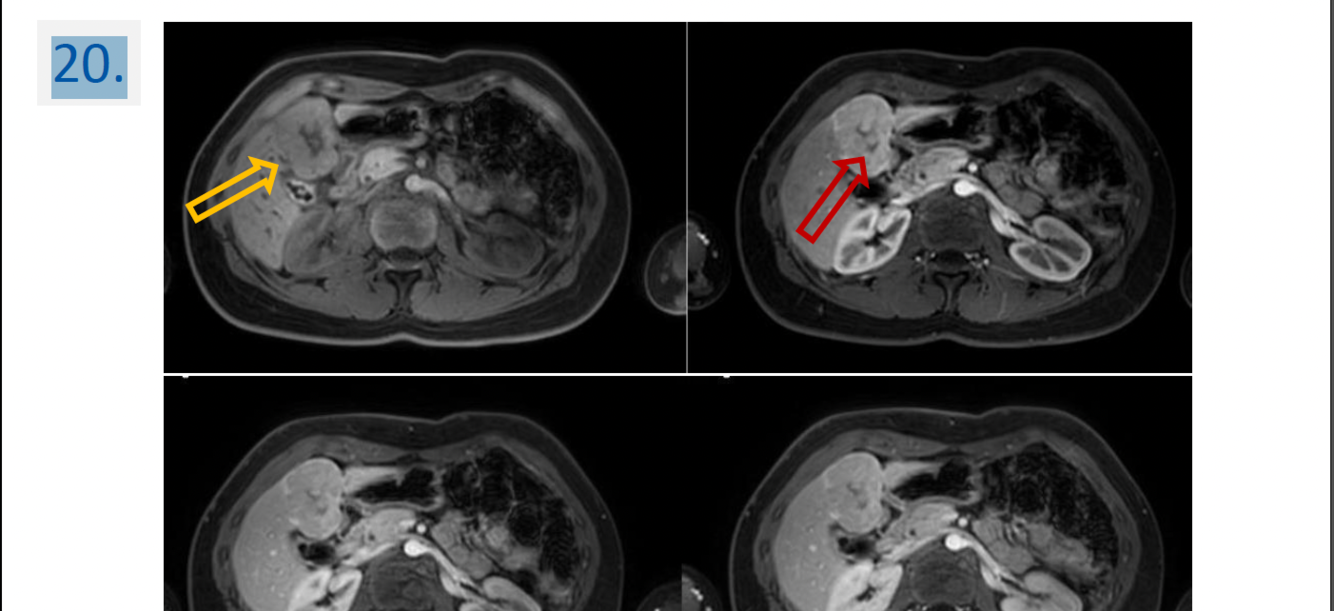

Modality:“mDIXON” dynamic contrast-enhanced MR after iv. gadolinium

(noncontrast, arterial phase, portal phase, venous phase)

Region:

upper abdominal MR study (axial view)

Diagnosis:

hepatic focal nodular hyperplasia (FNH)